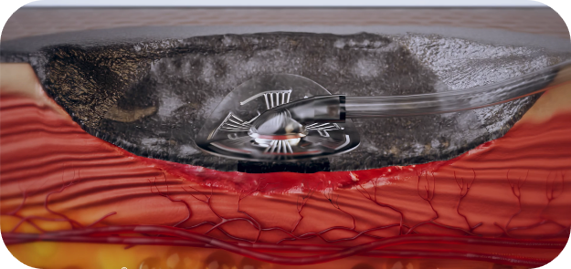

Werkingsmechanisme

De toepassing van negatieve druk met 3M™ V.A.C.® Therapie en 3M™ V.A.C.® Peel and Place-verband bevordert de wondgenezing door de vorming van granulatieweefsel en perfusie te stimuleren, exsudaat en infectiemateriaal te verwijderen, oedeem te verminderen en de wond voor te bereiden op sluiting.

Finite-elementanalyse suggereert dat het uitrekken van de cellen dieper plaatsvindt in het onderliggende en omliggende weefsel. Deze gestimuleerde cellulaire activiteit resulteerde in vergelijkbare of verhoogde belangrijke biomarkers voor wondgenezing die indicatief zijn voor de voortgang van de wondgenezing.

De unieke geïntegreerde en geperforeerde niet-klevende laag zorgt ervoor dat de gelijkmatige negatieve druk mechanische krachten buiten het wondbed naar het omliggende zachte weefsel kan uitoefenen en is veilig om tot 7 dagen te dragen.